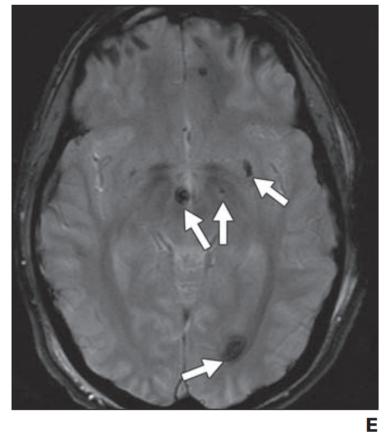

图7——肿瘤血管源性水肿。A,在伴有颅内黑色素瘤转移的1型水肿患者中,增强T1-加权图像显示右侧额叶和左侧顶叶的增强肿块(箭头)。B,FLAIR序列显示与A相同的病灶周围水肿,界限清楚,局限于肿块附近(箭头)。C,在多灶性多形性胶质母细胞瘤2型水肿患者中,对比增强T1加权成像显示左侧枕叶有多个强化病灶(箭头)。D,FLAIR序列显示弥漫性浸润性水肿(箭头),反映肿瘤微浸润。穿过胼胝体压部中线(星号)。

上图已经描述了两种不同类型的瘤周血管源性水肿。1 型可见于低级别和非神经胶质肿瘤的紧邻区域,例如脑膜瘤和转移瘤。这种类型被认为继发于脑实质压迫,继发性缺血和坏死甚至在肿瘤切除后仍然存在(图 7A )。2 型水肿发生在高度浸润性高级别神经胶质瘤中,会引起血脑屏障的额外紊乱。这种水肿模式遍及同侧大脑半球,指状突起反映肿瘤微浸润(图 7B )。切除后,数月内水肿可能会部分或完全消退。与 1 型水肿相比,2 型水肿 DWI 的扩散系数增加,DTI 的各向异性分数降低,这可能反映了恶性细胞浸润造成的实质破坏更大。当见于小肿瘤或良性肿瘤时,这种非典型水肿模式高度怀疑恶性变性。